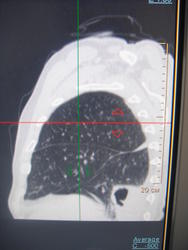

Больной лечился у невролога, провели проф ФГ- выявили деструктивную пневмонию, пролечилили, на Р контроле- ухудшение, клиники абсцесса не было, была боль в гр клетке спереди справа. Из анамнеза- лечился оперативно 6-7 лет назад по поводу рака верхней губы, в ООД не наблюдался последние годы. Данные за туб этиологию сомнительны, как мне кажется, очагов отсева по слоям не вижу,  хотя мож не так смотрю. Ваше мнение коллеги, абсцесс это или нет?

Спасибо, на послойных просмотрах тоже не увидела никаких отсевов. Хотя туб и онко отсевы ничем не отличались бы, да? Но СКТ должно и их отдифференцировать, чтобы больного направить на лечение по профилю.

Лабораторные данные у больного ничего не показали, все отрицательно-мбт 3 хкратно.